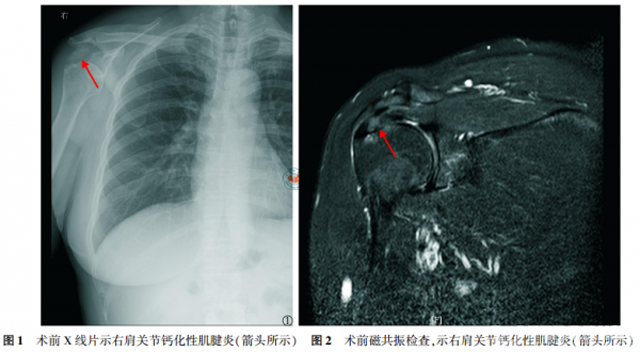

患者入院后减少患侧肩关节活动,予口服非甾体类消炎药(non-steroidal anti-inflammatory drugs,NSAIDs)药物西乐葆200 mg,一日两次,并予局部冰敷,收集术前美国加州大学肩关节评分(University of Californiaat Los Angeles,UCLA评分),完善相关检查,如肩关节X线检查(图1),肩关节磁共振检查(图2)和手术准备。

女性患者,49岁,因“右肩关节疼痛、活动受限5d”入院,查体见右肩关节局部压痛,以冈上肌处明显,右肩关节主动活动范围受限,被动活动范围基本正常,Neer撞击征(+),术前X线片示右肩峰下一巨大密度增高团块(图1),磁共振示右冈上肌腱内一信号增高团块(图2),诊断考虑“右肩关节钙化性肌腱炎”,行“右肩关节关节镜探查清理+冈上肌腱钙化灶清理+肩袖修补术”,术中清理右肩冈上肌腱内牙膏样的乳白色稠状物,即钙质沉积(图3),见肌腱裂口超过肩袖厚度的1/2,予2枚铆钉修补肩袖,术后复查右肩关节X片(图4)。术后患者疼痛程度明显减轻,随访9个月,UCLA评分由术前的11畅5分提高至33畅5分,且无出现术后并发症。